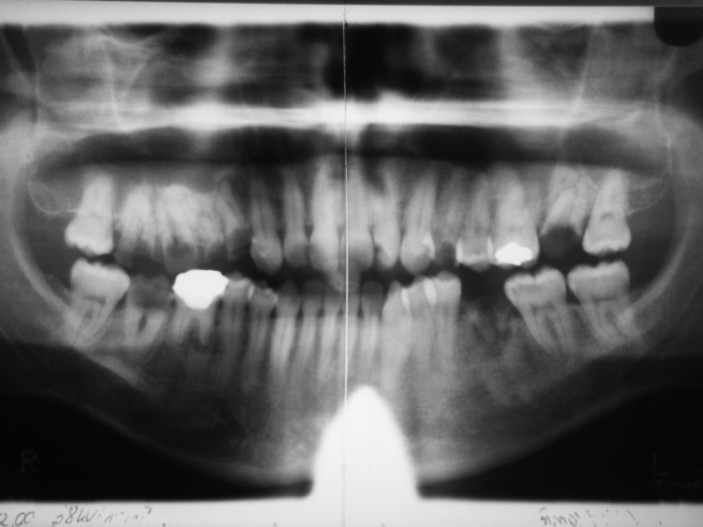

Da eine ausreichende Compliance seitens der Patientin als gesichert angesehen werden konnte, erfolgte zu diesem Zeitpunkt die Planung für die komplette Restauration des stark geschädigten Gebisses. Neben mehreren aufwendigen Extraktionen und Osteotomien der zerstörten Zähne erfolgte die Etablierung einer adäquaten Mundhygiene durch ein entsprechendes Prophylaxeprogramm. Die mit der Patientin vereinbarten Termine wurden von ihr konsequent eingehalten. Aufgrund starker beruflicher Beanspruchung umfasste die Vorbehandlung den Zeitraum eines Jahres (Abb. 2). An einer inzwischen völlig angstfreien Patientin konnte nun die abschließende prothetische Therapie vorgenommen werden. Insgesamt wurden zwei Brücken und eine Krone zur Wiederherstellung der Funktion und der Ästhetik eingegliedert (Abb. 3). Seit Abschluss der Gesamtsanierung befindet sich die Patientin im permanenten Recall zum langfristigen Erhalt des erreichten Zustandes.